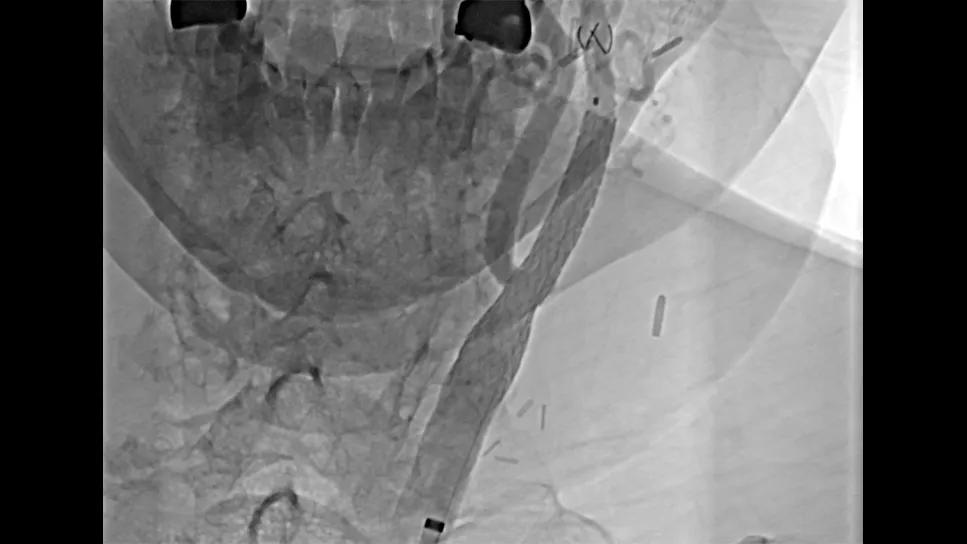

mesh stent in a carotid artery